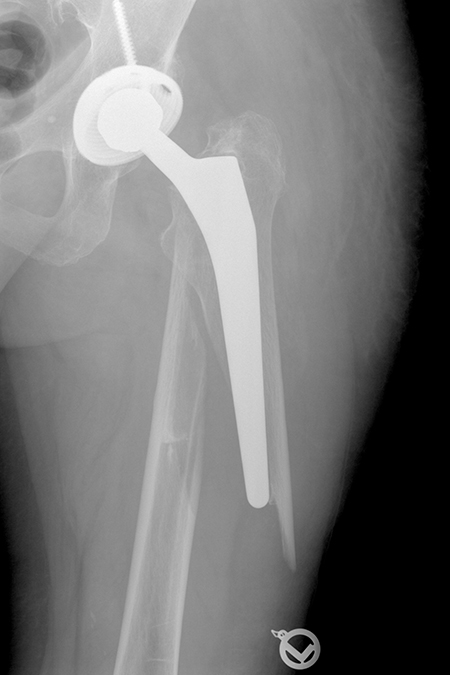

Ausgebrochener Prothesenschaft, der Knochen ist am unteren Ende nach außen abgespreizt (Vancouver B2).

Neu eingesetzter längerer modularer Hüftschaft mit anatomischer Fixierung des Knochenbruches durch Drähte.